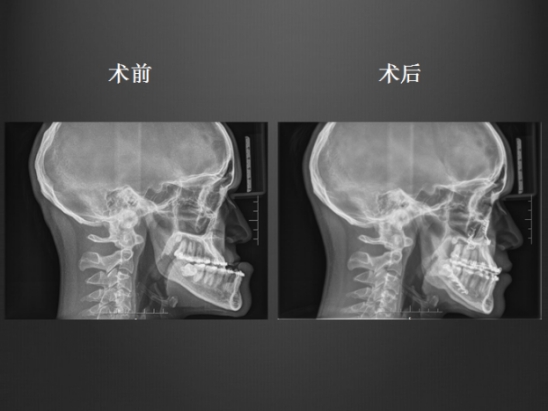

正颌外科手术病例